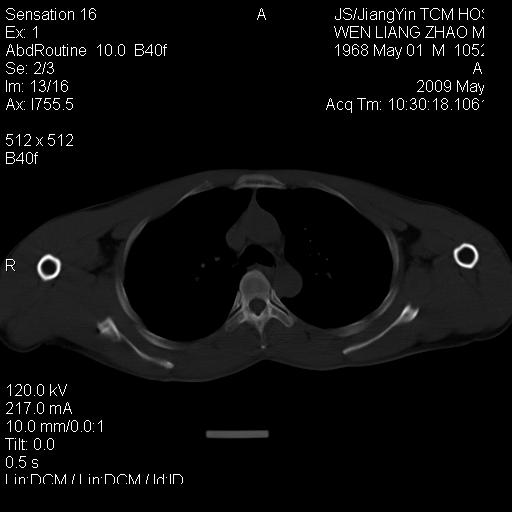

标题: CT19762:左侧喙突处压痛二年。考虑骨样骨瘤。 [打印本页]

标题: CT19762:左侧喙突处压痛二年。考虑骨样骨瘤。

左侧喙突处压痛二年。考虑骨样骨瘤。